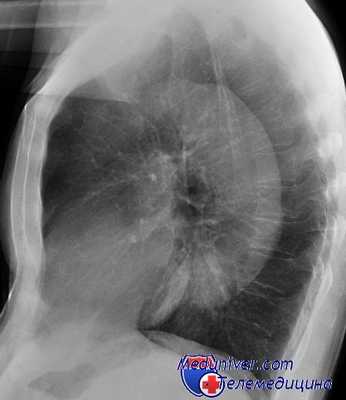

Газ, введенный в средостение, вначале распределяется в переднем его отделе, а затем спустя 1,5—2 часа переходит в заднее средостение. Последнему способствует то, что больной на 15—20 минут ложится на живот. Распределяясь в клетчатке средостения, газ бывает виден на рентгенограммах, так как он делает более заметными медиастинальные листки плевры, разъединяет органы, контрастно подчеркивая их границы, окружает сердце и крупные сосуды средостения.

Особенно хорошо заметна тень зобной железы, которая, располагаясь в виде подковы в верхнем отделе переднего средостения, отделяется полоской газа от дуги аорты. На пневмомедиастинограмме можно видеть тень пищевода и его стенки, трахею, легочную артерию. За последнее время нередко сочетают пневмомедиастинографию с томографией, что еще больше способствует детализации различных патологических процессов в средостении (А. Н. Кабанов).

Проводится тщательное рентгенологическое обследование (рентгенография грудной клетки, томография, рентгенография пищевода, пневмомедиастинография). Рентгенологически при медиастините может выявляться расширение тени шеи и средостения, эмфизема средостения, пневмоторакс, гидроторакс, уровень жидкости в средостении, пищеводные свищи.

- Лучевая диагностика. Обязательным методом обследования при подозрении на пневмомедиастинум является рентгенография грудной клетки в двух проекциях. На рентгеновских снимках определяются полосы газа, подчёркнута медиастинальная плевра, чётко очерчены контуры средостения. Анализ рентгенограмм в динамике позволяет выявить нарастание эмфиземы. В неясных случаях показана КТ грудной полости.